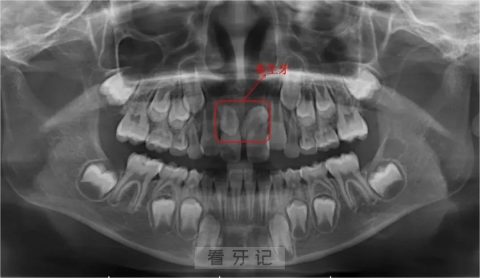

如果儿童的门牙出现迟迟不萌出或者异位萌出、门牙间存在较大缝隙且长期不关闭这些情况,家长可以先观察一段时间。

大多数情况下牙齿会自然生长,不用过分担心。当然我们也建议家长至少每半年带儿童来做一次口腔检查,排除多生牙的可能性。

其次,医生会根据多生牙的位置、形态、方向及对邻近组织的影响,以及患儿的年龄,来判断是否需要拔除,也就是要综合考虑拔除的必要性。

当多生牙在影响到恒牙正常萌出、导致恒牙发育异常、造成囊肿形成、导致恒牙牙根吸收、恒牙异位萌出、牙列不齐等症状时才应该进行拔除。